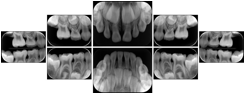

3. A dental provider wishes to capture a series of DICOM IO images for the patient’s dentition. The tooth morphology, teeth are divided into molars, premolars, canines and incisors, and a number of images for each jaw. The anatomic information was captured utilizing the triplet of schema. This standard code sequence is based on ISO 3950-2010, Dentistry - Designation system for teeth and areas of the oral cavity.

Every IO image should have anatomic information either through the primary or modifier sequence.

In most standard cases, images are oriented in structured layouts. These structured displays are useful to be shared between providers for reference purposes.